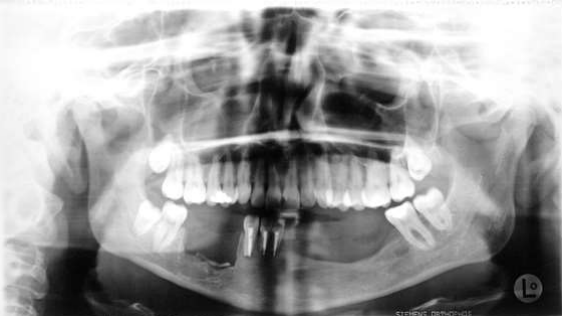

Fig 2: September 1993:  suspected recurrence regio 36-43: enucleation, anterograde root tip resection front lower jaw, filling with AAA-Bone: histology: desmoplastic fibroma

Fig 3:1994/04 suspected recurrence: crate-resection of the lower jaw, tooth extraction 44,45,46: histology: desmoplastic fibroma

Figure 2

Figure 3